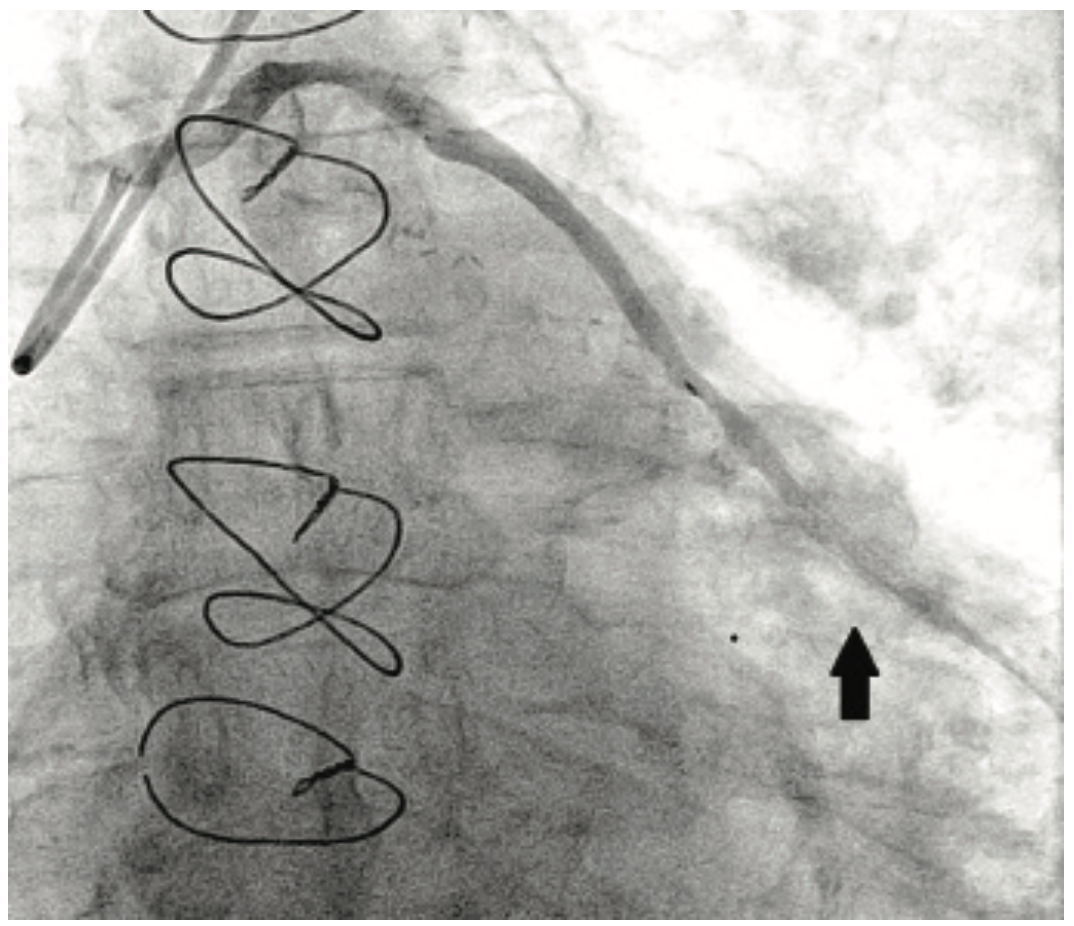

Left radial access was obtained with placement of a 6 Fr 10 cm Slender Glidesheath. Heparin and eptifibatide were used for anticoagulation. A 6 Fr Amplatz left (AL) 1 short tip guiding catheter (Cardinal Health) was used to provide extra backup support. Angiography demonstrated a diffuse subtotal in-stent restenosis of the distal SVG (Figure 4A). Laser atherectomy was performed with an X-80 excimer laser, followed by balloon angioplasty with 3.0 mm Angiosculpt scoring balloon and 3.5 NC Trek balloon (Abbott Vascular). Coronary brachytherapy was then administered using a 40 mm Beta-Cath source train, with a dwell time of 4 minutes, 48 seconds to deliver a dose of 23 Gray. The final angiographic result is shown in Figure 4B. The patient continues to do well post procedure and remains on dual antiplatelet therapy.

In contrast to the low profile and easy deliverability of current balloon catheters and stents, the Beta-Cath delivery catheter is a 3.5 Fr device, making it more difficult to deploy (Figure 5). The device requires a guiding catheter of at least 6 Fr. The compatibility with 6 Fr systems is desirable for use via transradial approach, since most radial arteries are not large enough to accommodate 7 Fr catheters.10,11 When using a 6 Fr guide, careful catheter selection for backup support and optimized lesion preparation are essential for procedural success. This was the rationale for the use of laser atherectomy in our two patients, as the goal is to achieve as ideal an angioplasty result as possible, without placing a new stent in the irradiated segment. The excimer X-80 laser catheter was used with three passes involving an incremental sequence of fluence (mJ/mm2) and repetition rate (pulses/second) of 60/60, 60/80, and 80/80.